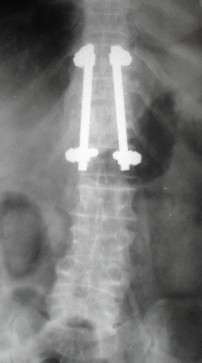

Case 1

68 y. old female

Diabetic

Discitis D 10 - 11

First stage anterior debridement and strut grafting.

Second stage posterior instrumentation and fusion.

Her neurology improved from Frankle B to D